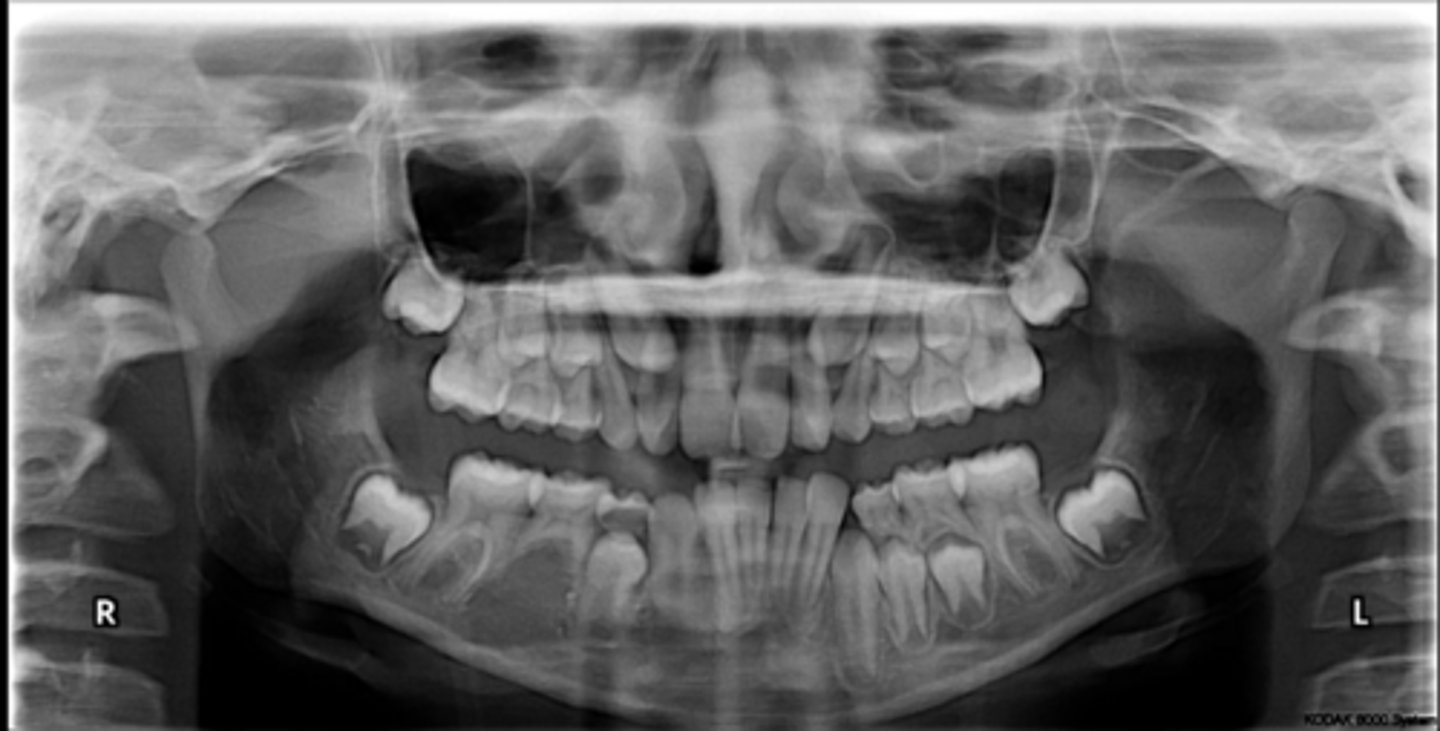

Premolar #13 (unerupted in pano) is more tilted than the opposing side (#4), which indicates an ectopic eruption pattern.

(Primary teeth w/o resorbing roots is also present)

What abnormalities/concerns do you see in this pano?

Third molars and mandibular right second premolar

Are there any congenitally missing teeth in the maxillary arch?

#29 (mandibular right second premolar)

Are there any congenitally missing teeth in the mandibular arch?

mandibular right second molar

Are there any retained primary teeth?

maxillary canines

Are there any impacted teeth?

Yes

Is there crowding?

More or less

Are the condyles symmetrical?

Maybe?

Is there any pathology?

Are there any ankylosed primary teeth?

No, just one in an odd position

Is there any ectopic eruption?

No

Are there supernumerary teeth?